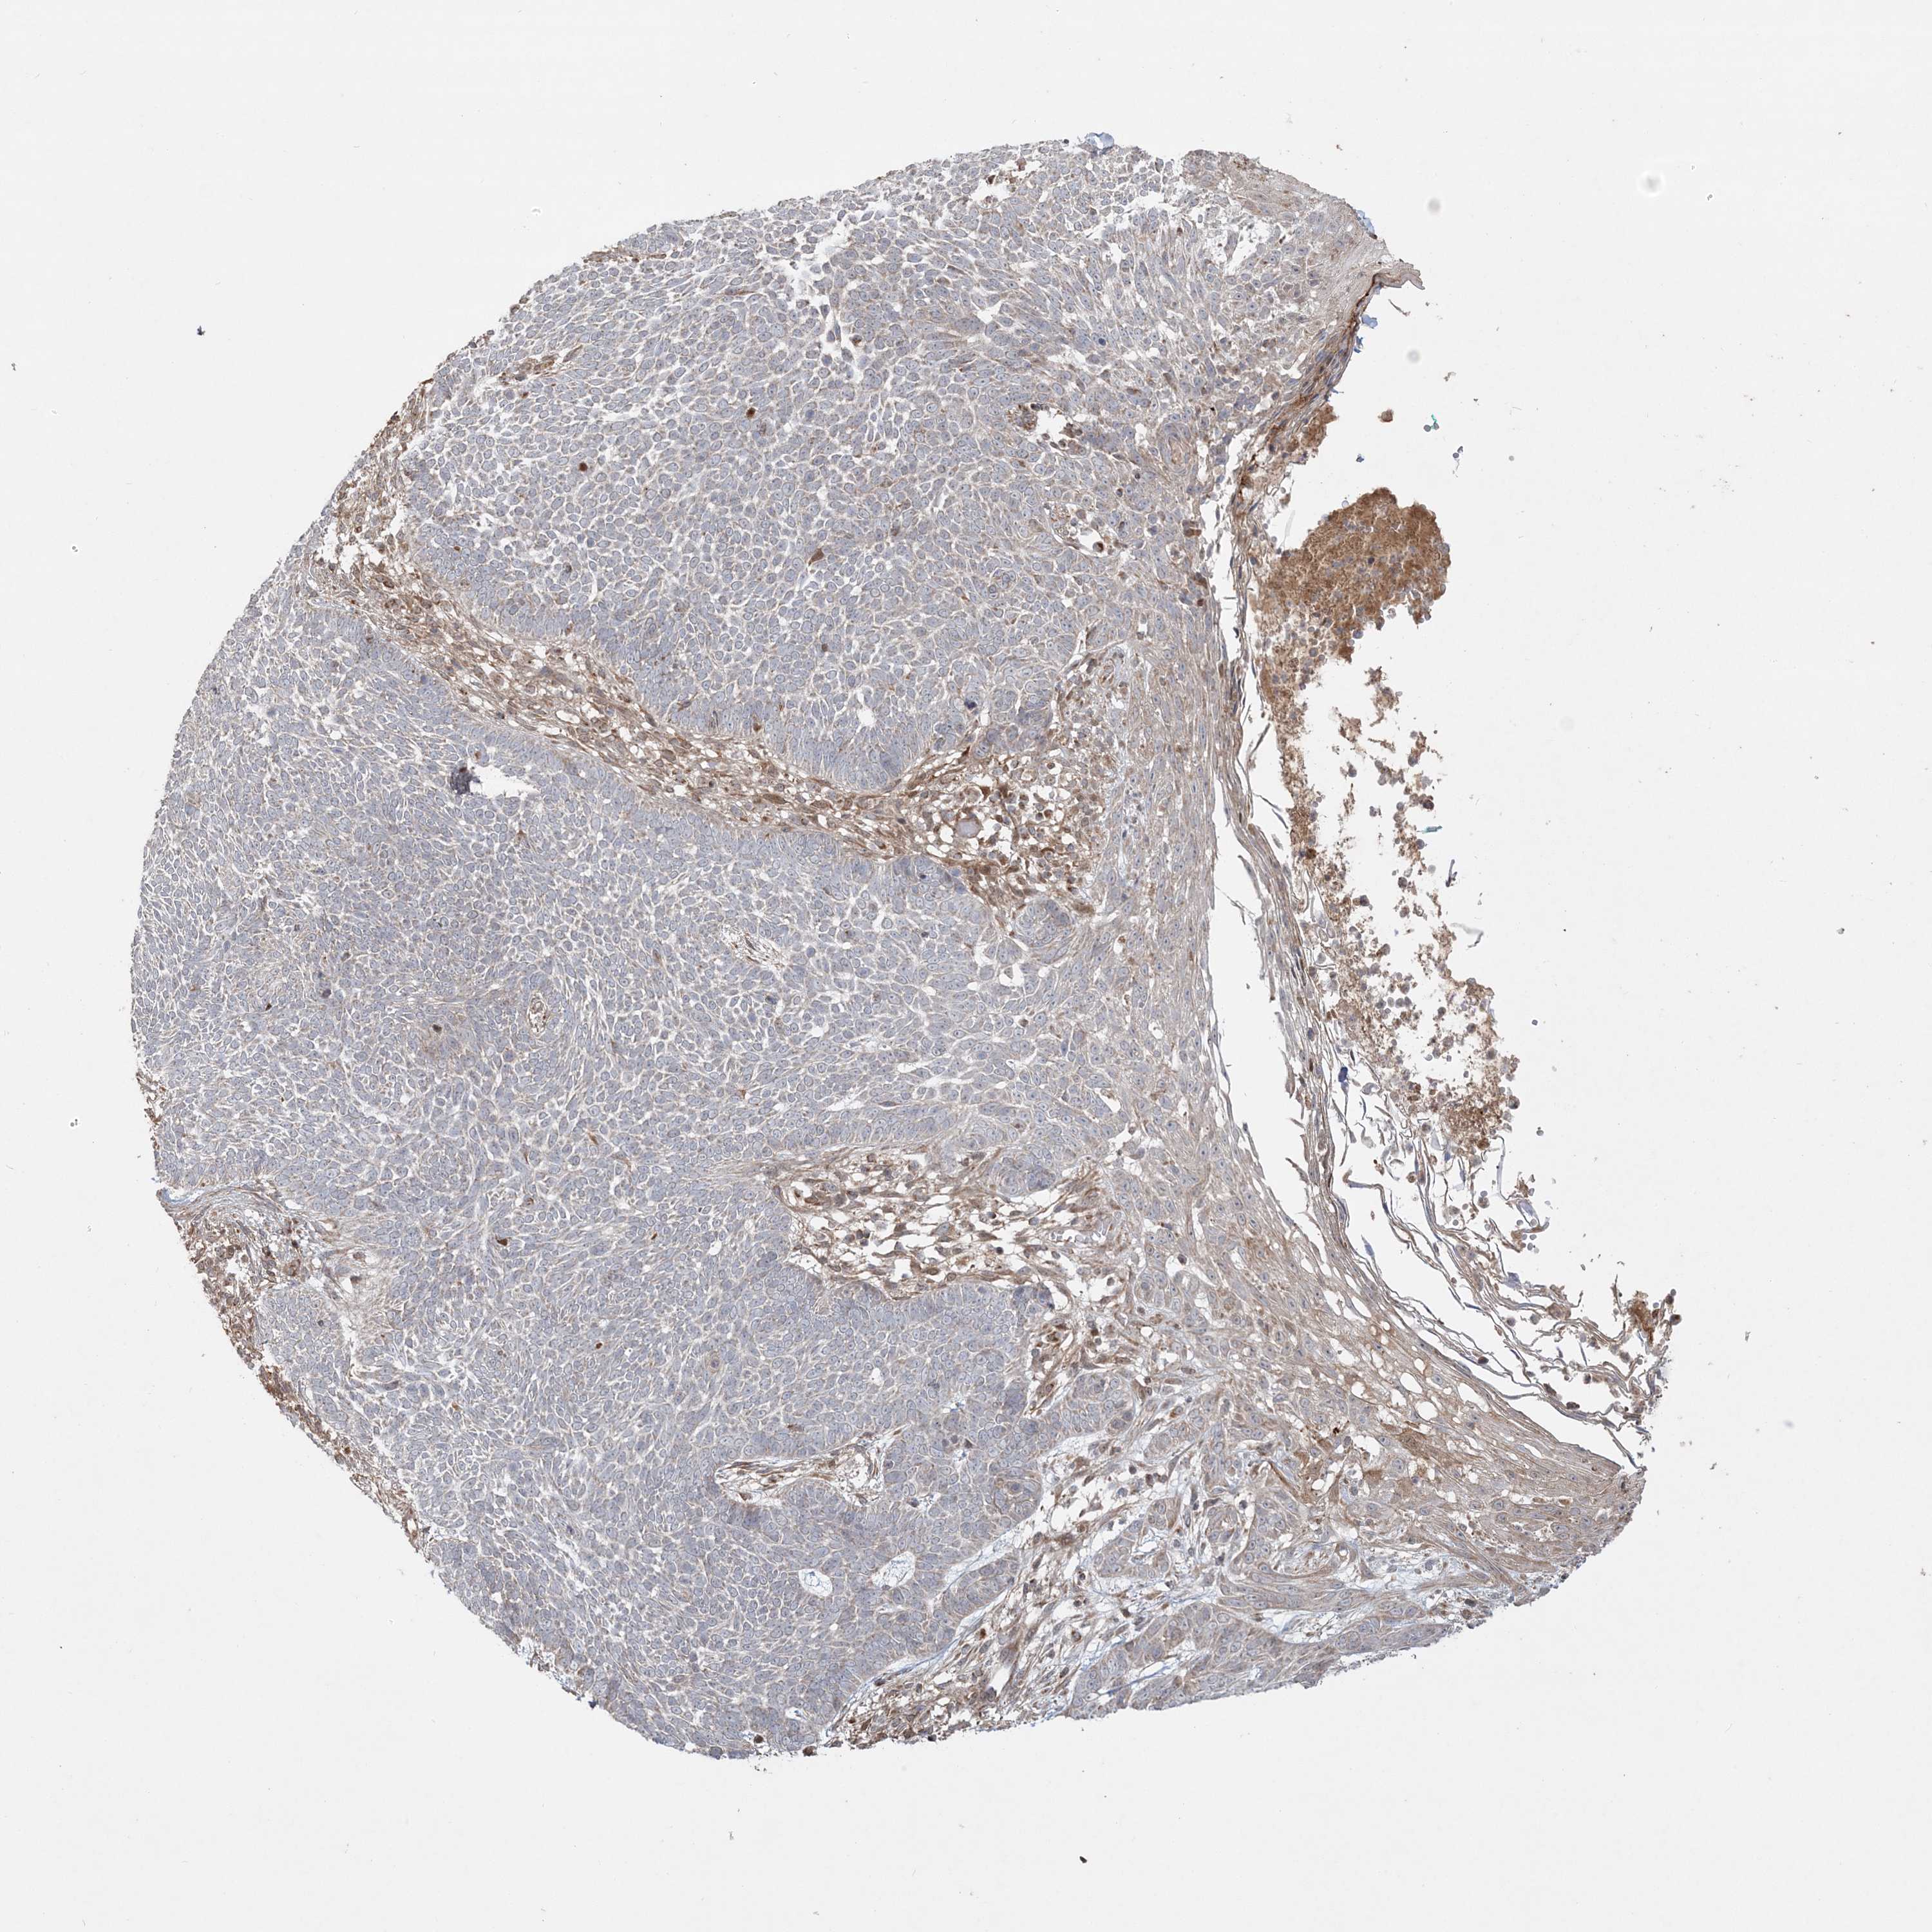

Basal cell and squamous cell cancer

SKIN CANCER - Protein expressioni

A mouse-over function shows sample information and annotation data. Click on an image to view it in a full screen mode. Samples can be filtered based on level of antibody staining by selecting one or several of the following categories: high, medium, low and not detected. The assay and annotation is described here.

Each image is clickable and will lead to virtual microscopy that enables deeper exploration of all samples and also displays staining intensity scores, fraction scores and subcellular localization as well as patient and tissue information for each sample.

Antibody HPA036560

Basal cell carcinoma

Squamous cell carcinoma, NOS

Squamous cell carcinoma, metastatic, NOS